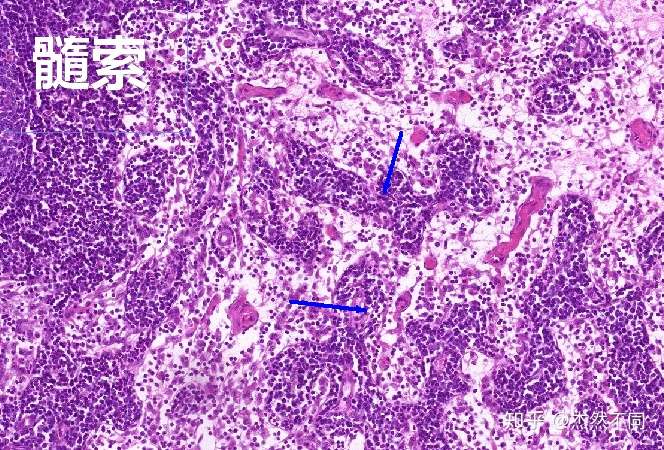

淋巴结(髓质)

图片尺寸1080x810